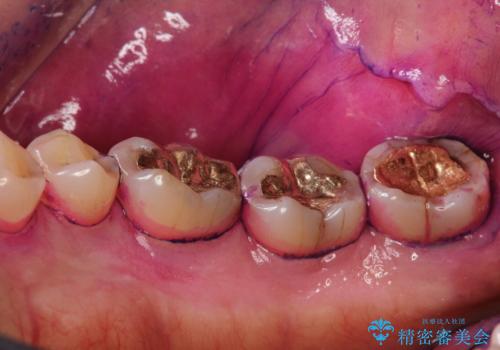

しかし、プラークは歯の色と似ているため、見ただけでは付着しているかどうかがハッキリとは分かりません。

染め出し液を使ってプラークを染め出すことにより、普段の歯みがきで磨き残している場所を目で確かめることができます。

日々の歯磨きを上達するには、まずどこが磨けていないか認識することが大切です。